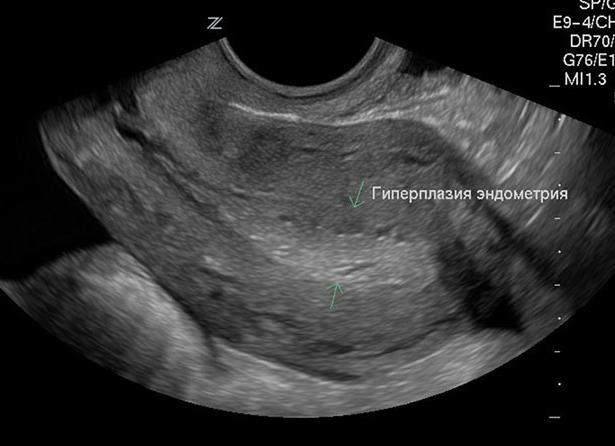

Эхопризнаки гиперплазии эндометрия в менопаузе

Гиперплазией эндометрия называется патологическое разрастание слизистого слоя матки в полость детородного органа или мышечную ткань.

Визуально оценить состояние матки можно при помощи ультразвукового мониторинга. В естественном климаксе сканирование показывает, что толщина слизистого слоя составляет менее 5 мм. При этом матка имеет правильную форму, не увеличена, а в мышечной прослойке нет патологических включений.

Железистая гиперплазия характеризуется преимущественным разрастанием слизистой ткани, повышением уровня эндометрия. Во время ультразвукового исследования можно обнаружить, что внутренний слой имеет толщину более 5 мм на всем своем протяжении.